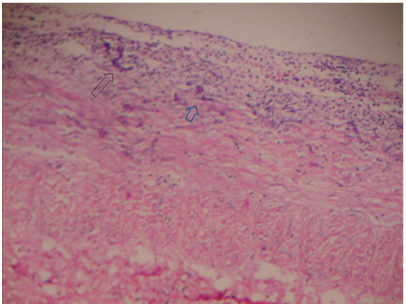

On tenth day of life, he developed feeding intolerance and per rectal bleeding. A soft to firm lump of about 2×3 cm in size was palpable in the right hypochondriac region. Nasogastric tube aspirate was bilious. Erect X-ray abdomen showed dilated stomach with paucity of gas in lower abdomen and pelvis (Figure 1). Dye study done for confirmation of diagnosis showed the same picture i.e. only gastric shadow could be visualized. Ultrasonography of the abdomen showed dilated, peristaltic bowel loops. Haematologic investigations showed raised WBC counts of 16,000/cmm and low Platelet count of 100,000/cmm. The differential diagnosis was malrotation with volvulus or necrotizing enterocolitis. In view of poor general condition, the child was explored under local anaesthesia. He had characteristic black-velvety gangrene confined to middle 8-10 cm of the mid-transverse colon without any frank / impending perforation. Initial 5-7 cm of mid-transverse colon from the hepatic flexure was normal. Rest of the colon and small bowel was healthy looking. The non-viable colon was excised. After resection, the free ends were brought out as colostomy and mucus fistula through either end of the incision. Blood loss of about 20 cc was replaced on table. Post-operatively the activity improved. Nasogartric feeds were started on post-operative day three, once colostomy was functioning. Initially they were well-tolerated.

Figure 1 Erect X-ray abdomen showed dilated stomach with paucity of gas in lower abdomen and pelvis.